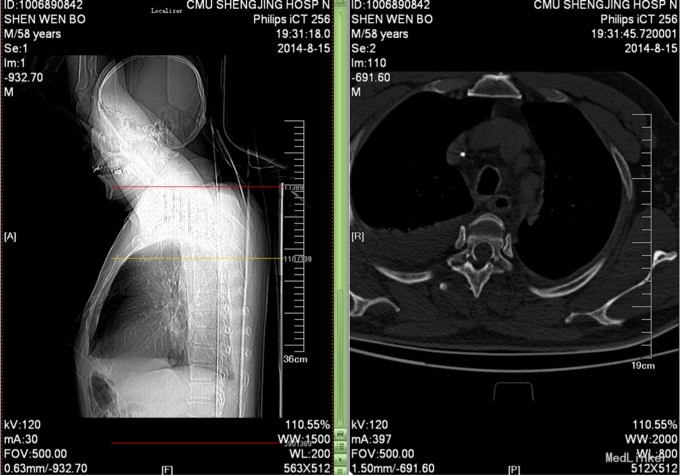

患者于2014-08-13日11:30左右骑摩托车摔倒,伤后一过性意识不清,清醒后感觉胸部疼痛,双下肢活动受限,急诊送至盘锦市宽甸县中心医院,行胸CT、头CT、胸椎三维CT,提示为胸椎骨折,急诊行面部伤口清创缝合,具体治疗不详。患者及家属为求系统治疗,急来我院,急诊予以行辅助检查,提示:胸椎骨折;急诊以“多发外伤”为主诊断收入我科.

诊断:胸3-6椎体骨折,胸髓损伤,双下肢全瘫。 入院后完善检查,查无手术禁忌症后行胸椎骨折后路切开复位椎板减压椎弓根钉内固定术